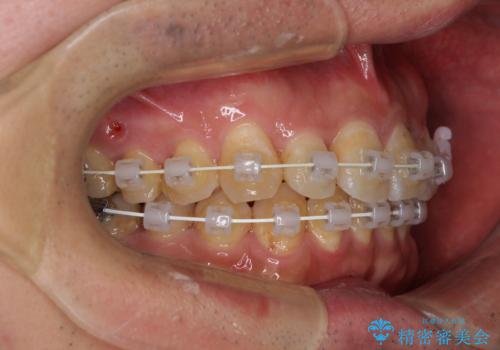

上顎前歯が舌側に転位しており、なるべく早く楽に矯正したいとのことで、ワイヤー矯正を行うこととしました。

虫歯治療途中の歯は仮歯が装着されていたため、そのまま矯正治療を行い、矯正後に補綴治療を行うこととしました。

インビザライン矯正では苦手とする舌側転位した前歯をスムーズに改善することができました。